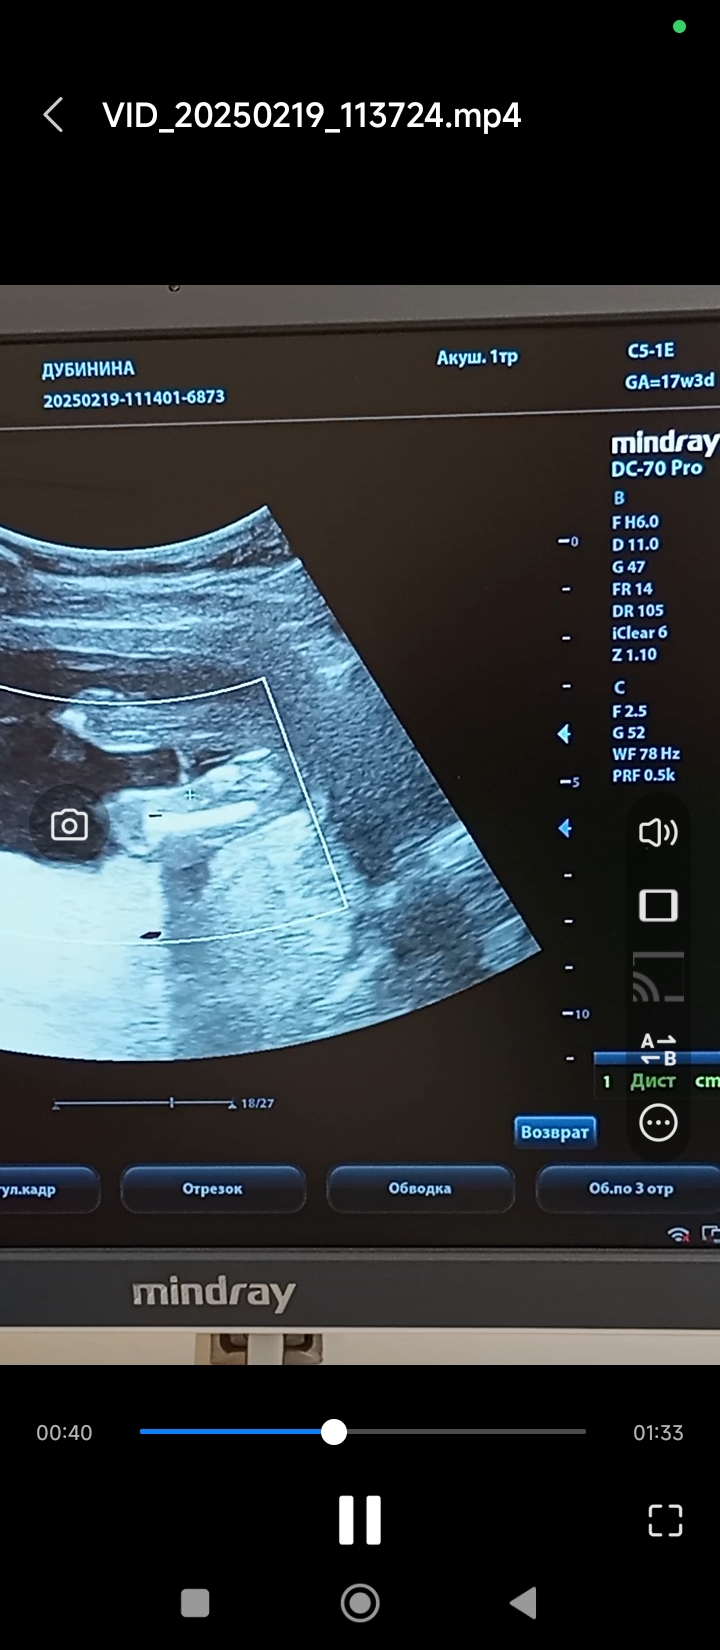

Валентина в Благополучная беременность 9 месяцев Пол Пол малыша Пол на 17 недели. Кто там? Посмотрите еще 20 записей на эту тему Отменить Ответить Ирина Лапина Мальчик🙂 27.02.2025 Ответить Чашка утреннего кофе Мальчик - мошонку видно, у девочек такого нет)) 27.02.2025 Ответить Валентина Чашка утреннего кофе, 27.02.2025 Ответить Виктория Я думаю девочка, у мальчиков сильнее торчит) 27.02.2025 Ответить Валентина Виктория, 27.02.2025 Ответить Виктория Валентина, девочка) 27.02.2025 Ответить Tatiana И я за мальчика. 27.02.2025 Ответить Ornella Mutit Предположу мальчика🩵 27.02.2025 Ответить Mari Я думаю мальчишка) у моей на таком же фото ничего не было между ножек) . 27.02.2025 Ответить Валентина Mari, здесь тоже ничего нет 27.02.2025 Ответить Mari Валентина, значит на том фото показалось) мелкое очень. Теперь вижу, что ничего нет) ну значит, девочка☺ 27.02.2025 Ответить Виктория Я за девочку 27.02.2025 Ответить Юля А мне кажется что мальчик ... 27.02.2025 Ответить Татьяна Мне кажется девочка 😁 У моего на такой фотке прям торчал корнишон😆 27.02.2025 Ответить Мальчик же? Пол мальчик или девочка? Чаты Беременных Выберите чат: Январята-2026 Февралята-2026 Мартята-2026 Апрелята-2026 Майчата-2026 Июнята-2026 Июлята-2026 Августята-2026